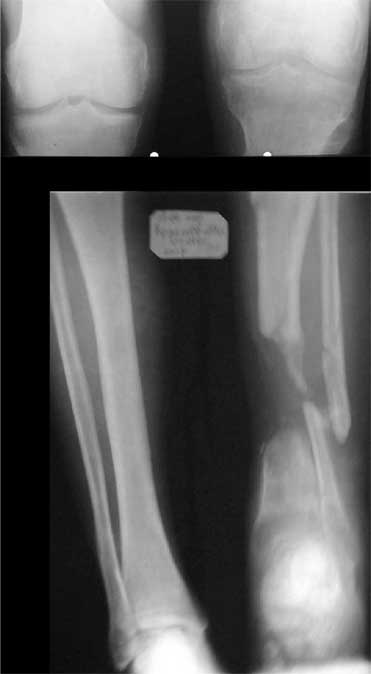

В приложении - моё наблюдение (возможно, уже представлял, тогда

извините).

Нога попала в пресс.

Ко мне больной попал черз 1,5-2 года после травмы и нескольких

операций с синегнойной инфекцией на всю голень. Меня пригласили на консультацию

насчет ампутации.

Лечил я его месяцев 8.

Малоберцовка полностью перестроилась, нога опороспособна.

При ходьбе на дальние расстояния пользуется тростью.

Осталась трофическая язва, периодически закрывается.

Клинические снимки где-то есть, но не очень качественные.

Один из вариантов.